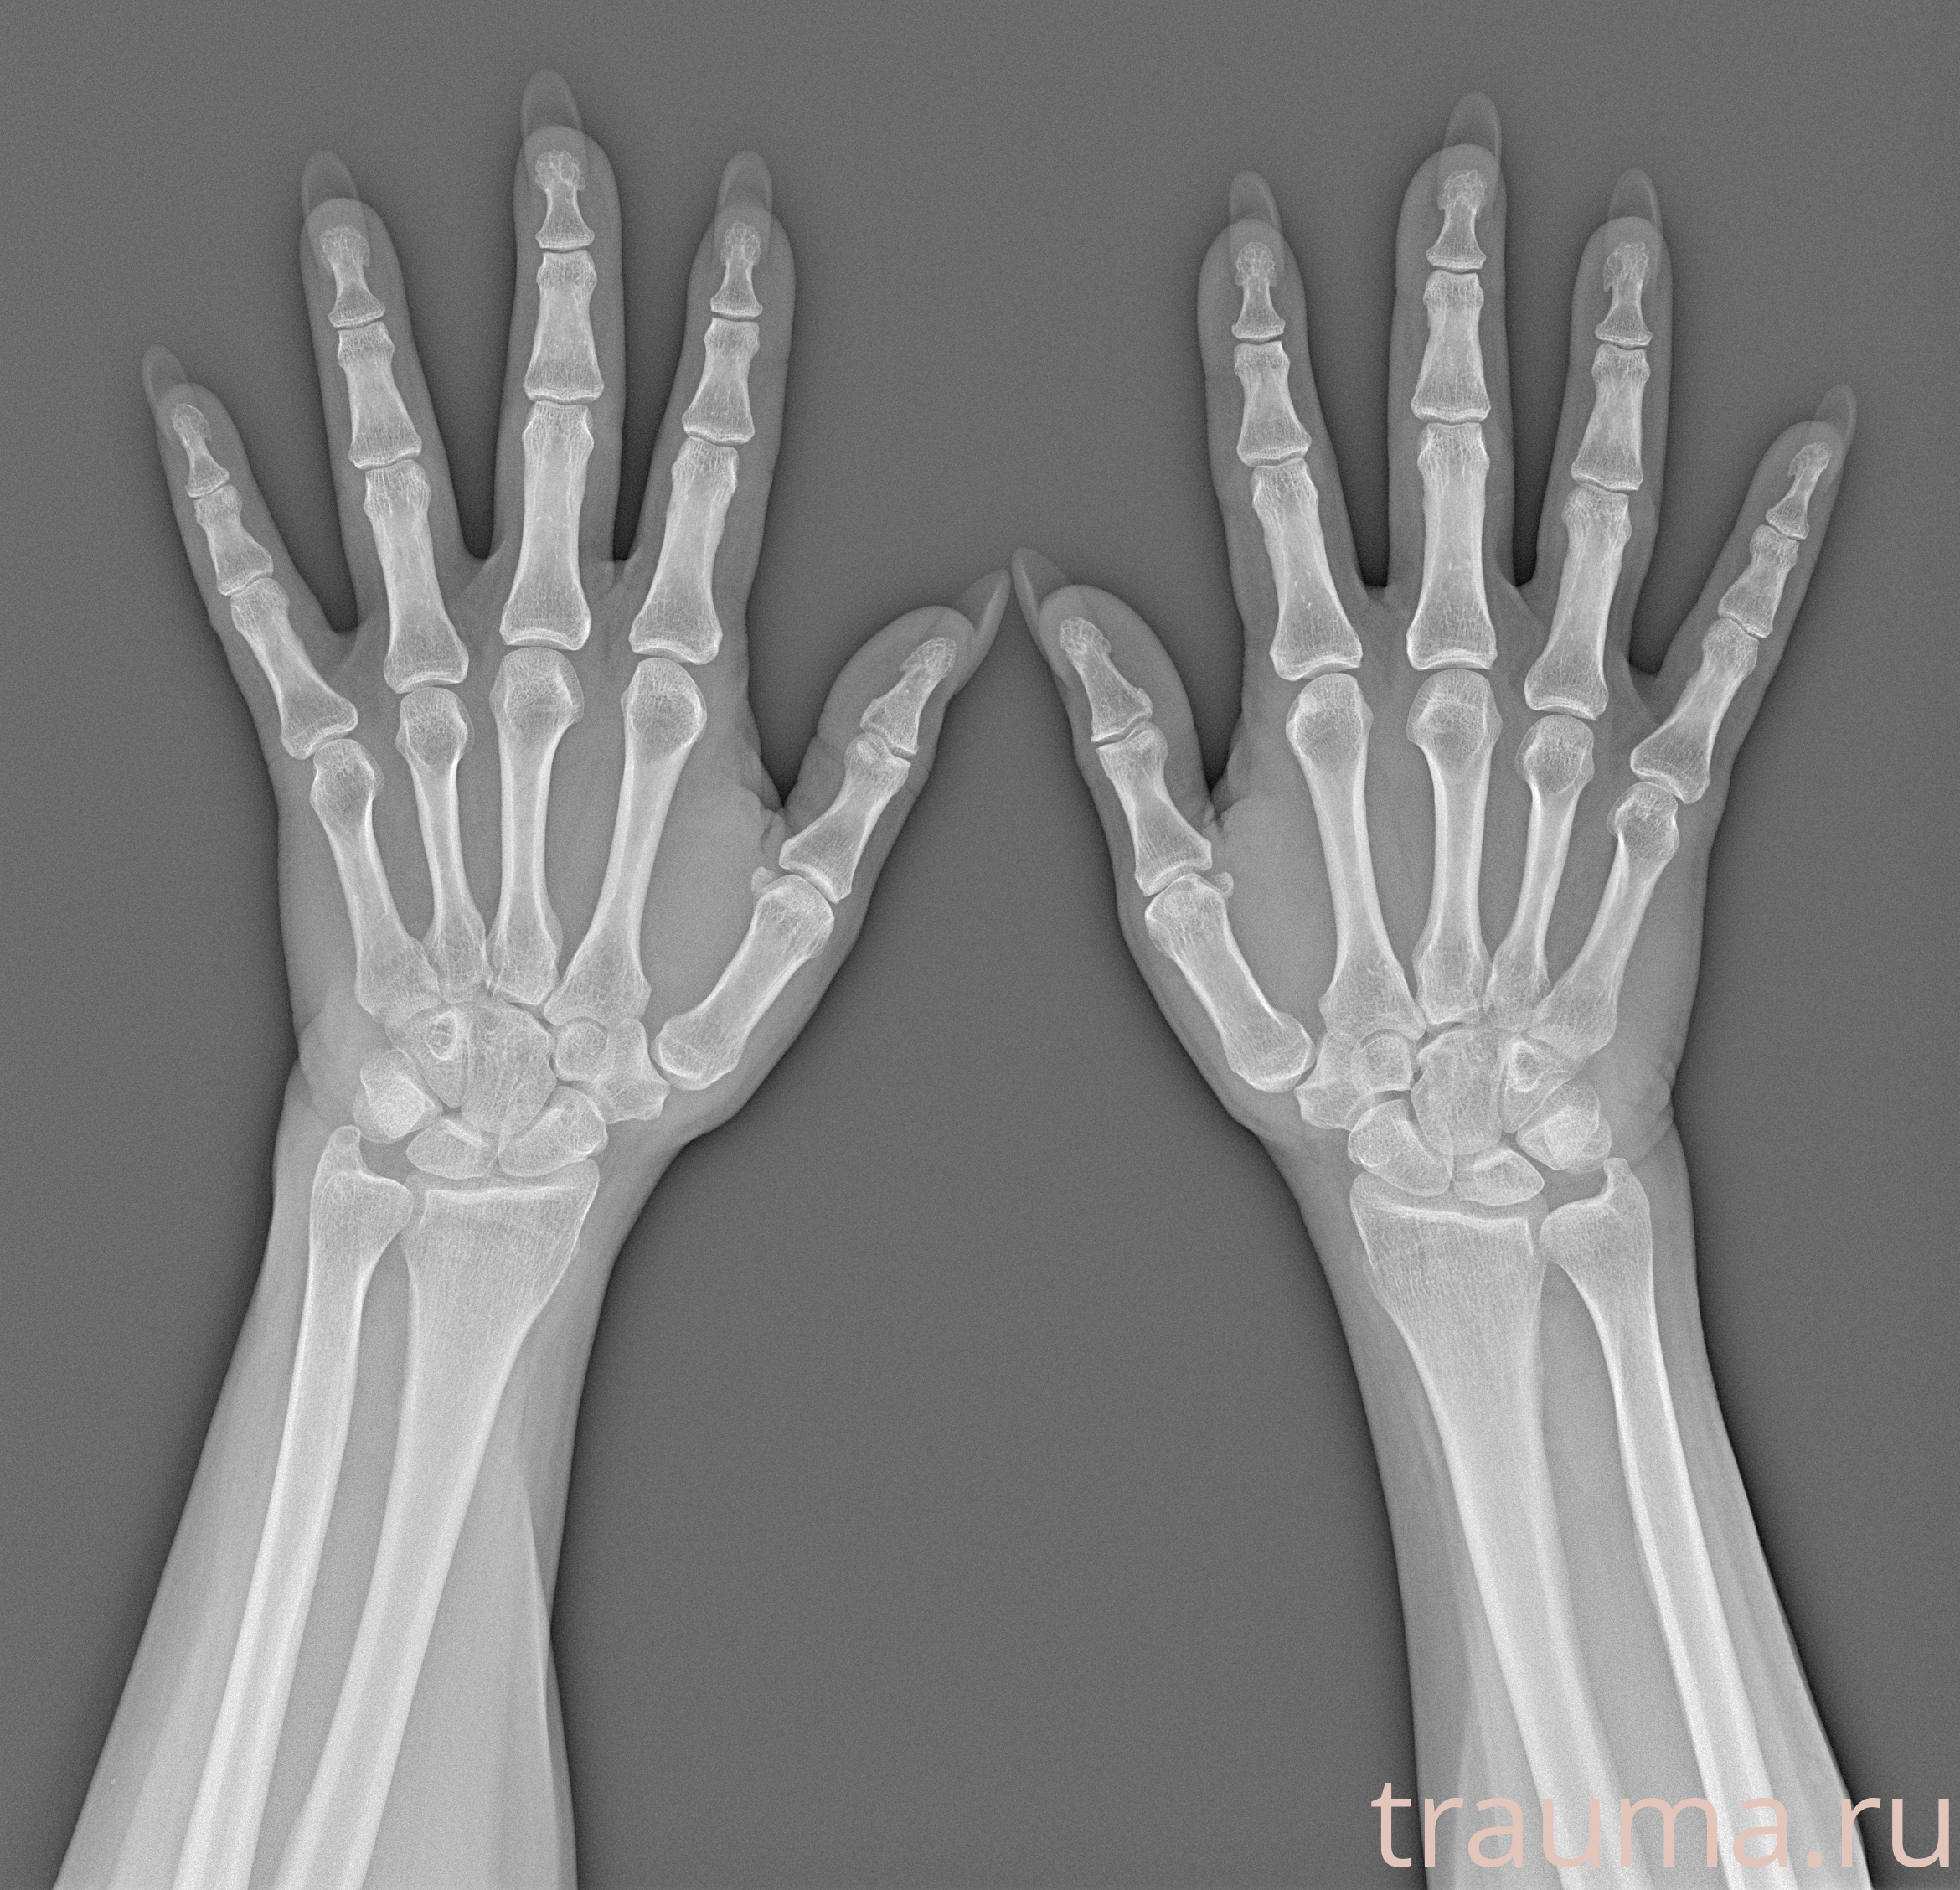

Рентгенограммы

Рентген на дому: по вашему адресу приезжает врач-рентгенолог, травматолог-ортопед с мобильным рентгеновским аппаратом, проводит диагностику травмы или заболевания, делает необходимые рентгенограммы, дает рекомендации по дальнейшему лечению. Получить качественные снимки в домашних условиях возможно благодаря уникальной методике, разработанной МосРентген Центром для института  Склифосовского